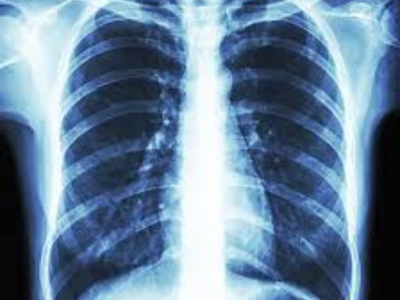

Digital X-ray and Ultrasound Facilities

Real-time imaging helps in diagnosis, monitoring, as well as guiding intervention if needed.